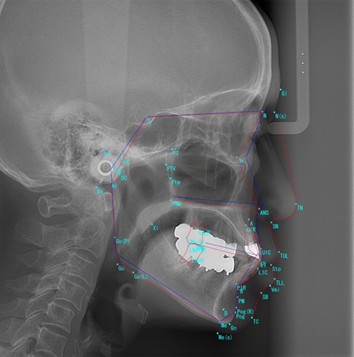

3.矯正治療に欠かせない『セファログラム』(矯正用頭部X線撮影)

セファログラム(頭部X線規格写真)は、骨格と歯の関係を詳細に分析し、適切な治療計画の立案や治療効果の客観的評価に欠かせないX線検査です。

セファログラムの種類と分析内容

セファログラムには、「側面セファログラム」と「正面セファログラム」の2種類があります。

| 種類 | 分析できる内容 |

|---|---|

| 側面セファログラム | 顎の前後的な関係、歯の傾斜角度、上顎と下顎の位置バランス |

| 正面セファログラム | 顔の左右対称性、顎の幅、上下顎の横方向のバランス |

セファログラムの分析(セファロ分析)

セファログラムでは、X線写真に基準点を設定し、角度や距離を測定することで骨格や歯の位置関係を数値化します。

これにより、正確な診断や矯正治療の計画を立てるための重要な情報を得ることができます。

側面セファログラム

セファロ分析でわかること

- 顎の骨格やズレの状態

上下の顎の位置関係を確認し、出っ歯や受け口などのズレの程度を診断します。

- 歯並びのバランス

歯の傾きや配置を分析し、矯正装置を装着する際の判断材料になります。

- 顔のバランス

横顔の骨格や、上下顎のバランスを確認できます。